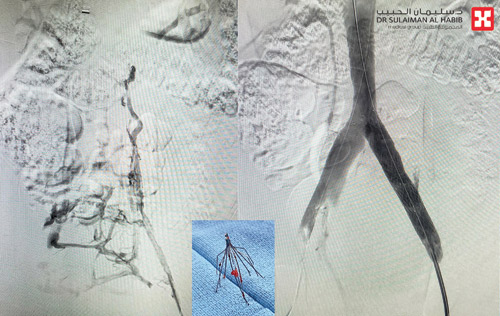

وقال د. البشري أن المريضة قدمت إلى المستشفى بعد محاولات علاج كثيرة لم يكتب لها النجاح، وفي إحداها تمت زراعة فلتر في الوريد الأجوف السفلي لكن الفلتر تحرك من مكانه مما زاد من تعقيد حالتها، واعتذر الأطباء في عدة مستشفيات عن علاجها. وأضاف أن الفحوصات الدقيقة التي أجراها المستشفى أظهرت وجود جلطات بالأطراف السفلية، إضافة إلى أن الفلتر تحرك من مكانه للأسفل، وخرج من الوريد الأجوف السفلي وانغمس في جدار الوريد الخارجي، وبعد دراسة الحالة وضع الفريق الطبي خطة علاجية، وأجريت لها عملية تم فيها أولاً إزالة الفلتر عبر تقنية القسطرة دون جراحة، ثم فتح الوريدين الأيسر والأيمن، وتركيب دعامتين في الأيسر للتخلص بشكل كلي من الضغط الذي يسبب الجلطات، ومضى التدخل الطبي دون أي مضاعفات، وانتهت ولله الحمد بالنجاح التام.